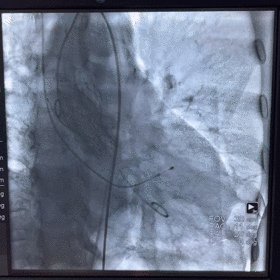

术中影像

图片

根部造影

球囊预扩

释放瓣膜

瓣膜释放至2/3造影观察

瓣膜释放完毕

手术结果

术后造影及超声探查未见瓣周漏,跨瓣压差术前108mmHg,术后几乎无压差,术中及术后未出现相关并发症,手术圆满完成。